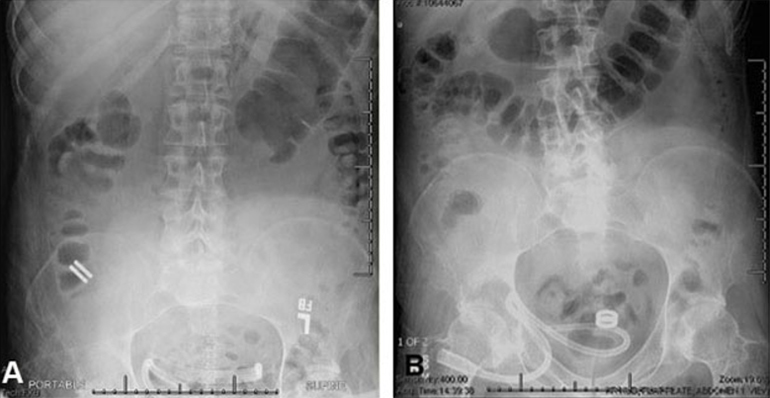

The study, led by Principal Investigator Michael Harrison, MD, is a prospective, single-center, first-in-human pilot clinical trial to evaluate the feasibility and safety of creating an intestinal anastomosis using the Magnamosis device. Magnetic compression anastomosis (magnamosis) uses a pair of self-centering magnetic "Harrison Rings" to create an intestinal anastomosis without sutures or staples. Each magnet is placed within the lumen of a desired segment of the intestine and brought together, or “mated.” The magnetic force on the compressed tissue causes necrosis and an anastomosis forms. The magnets then pass through the bowel.